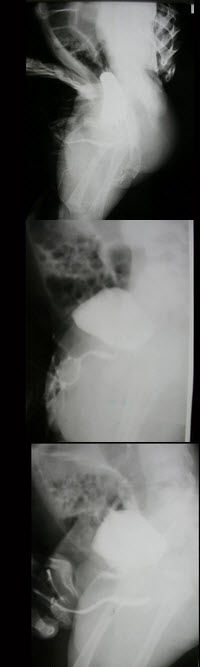

24、单项选择题

男,40岁,腹胀痛1月余。体检:脾肋下5cm,结合图像,最可能的诊断为()

A.正常食管

B.食管静脉曲张

C.食管胃底静脉曲张

D.贲门失弛缓

E.食管癌